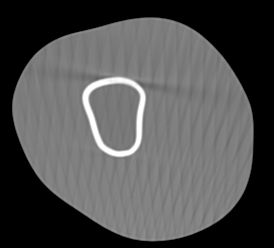

Involuntary subject motion is the main source of artifacts in weight-bearing cone-beam CT of the knee. To achieve image quality for clinical diagnosis, the motion needs to be compensated. We propose to use inertial measurement units (IMUs) attached to the leg for motion estimation. We perform a simulation study using real motion recorded with an optical tracking system. Three IMU-based correction approaches are evaluated, namely rigid motion correction, non-rigid 2D projection deformation and non-rigid 3D dynamic reconstruction. We present an initialization process based on the system geometry. With an IMU noise simulation, we investigate the applicability of the proposed methods in real applications. All proposed IMU-based approaches correct motion at least as good as a state-of-the-art marker-based approach. The structural similarity index and the root mean squared error between motion-free and motion corrected volumes are improved by 24-35% and 78-85%, respectively, compared with the uncorrected case. The noise analysis shows that the noise levels of commercially available IMUs need to be improved by a factor of $10^5$ which is currently only achieved by specialized hardware not robust enough for the application. The presented study confirms the feasibility of this novel approach and defines improvements necessary for a real application.